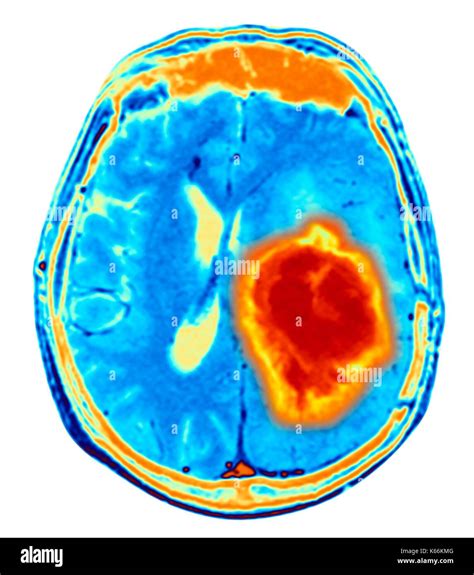

When a physician suspects an abnormality within the skull, a Brain Neoplasm MRI is the gold standard diagnostic tool used to visualize the intricate structures of the brain. Neoplasms, or abnormal tissue growths, can be benign or malignant, and magnetic resonance imaging (MRI) provides unparalleled detail to distinguish between these possibilities. By utilizing powerful magnets and radio waves rather than ionizing radiation, MRI technology produces high-resolution, cross-sectional images that allow radiologists and neurosurgeons to pinpoint the exact location, size, and characteristics of a potential tumor.

A standard Brain Neoplasm MRI protocol involves several different "sequences" or scan types. Each sequence is designed to highlight different biological features of the tissue. For example, T1-weighted images are excellent for anatomical detail, while T2-weighted and FLAIR (Fluid-Attenuated Inversion Recovery) images are highly sensitive to identifying edema or inflammation around a mass.

To improve the diagnostic accuracy, doctors often use a gadolinium-based contrast agent. When injected intravenously, this contrast material accumulates in areas where the blood-brain barrier is compromised, which is typical in many types of neoplasms. This "enhancement" helps doctors clearly delineate the tumor from healthy brain tissue.

Interpreting the Results